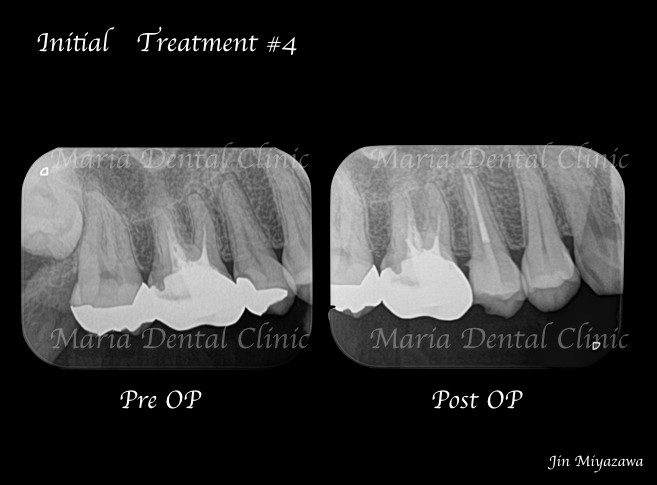

診査の結果、右上5番の歯髄には歯髄生活反応は確認できず、歯髄壊死が起因となる根尖性歯周炎と診断しました。術前のレントゲン診査により、根尖が2つに分岐していることを確認できます。

*赤丸で示しているところは、根が分岐している箇所を示す

今回は右上5番に対しての根管治療における、根尖3mmで分岐する根管へのアプローチでした。

一度見失った根管は通常の根管治療では追従が難しくなるため、感染を根管内に留めてしまう原因となります。その為、術前のレントゲン診査が非常に重要となります。